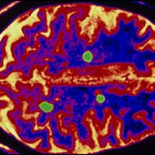

Hallan clave para revertir la esclerosis múltiple

Investigadores de las universidades de Cambridge, Inglaterra y Edinburgo, Escocia, descubrieron que activando las células madre cerebrales se puede regenerar a la mielina, la vaina que protege a las prolongaciones de las neuronas -llamadas axones- encargadas de transmitir los impulsos nerviosos. La EM se produce cuando la pérdida de la vaina de mielina, que actúa como una capa aislante, conduce a daños en los axones, lo que a su vez provoca alteraciones en el envío de mensajes desde el cerebro a otras partes del cuerpo.